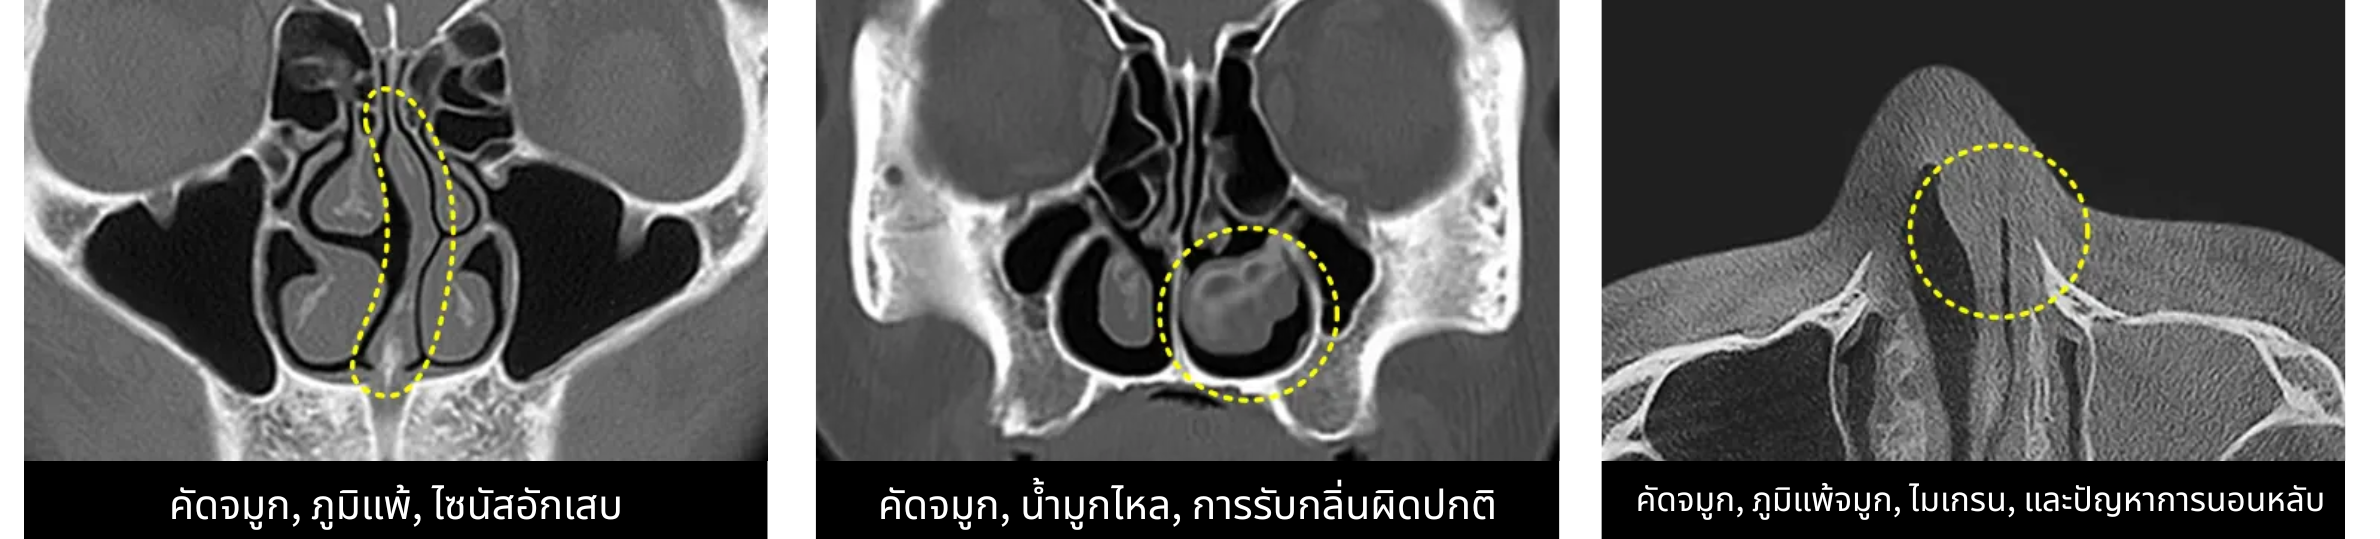

5️⃣ ใช้คลื่น RF ภายในโพรงจมูก

คลื่น RF (Radio Frequency) เป็นเทคโนโลยีที่ใช้พลังงานความถี่วิทยุเข้าไปกระตุ้นเนื้อเยื่อภายในโพรงจมูก จุดประสงค์หลักคือ ลดพังผืด และป้องกันการหดรั้งของเนื้อจมูกหลังผ่าตัด ซึ่งมักเป็นสาเหตุของจมูกเบี้ยวหรือผิดรูปในระยะยาว การใช้ RF ยังช่วยให้รูจมูกทั้งสองข้างเปิดเท่ากัน ลดการอุดตัน และช่วยให้หายใจสะดวกขึ้น สำหรับเคสของเด่นคุณ เทคนิคนี้ถูกใช้เพื่อช่วยให้หายใจดีขึ้น และลดปัญหาการกรนขณะนอนหลับ